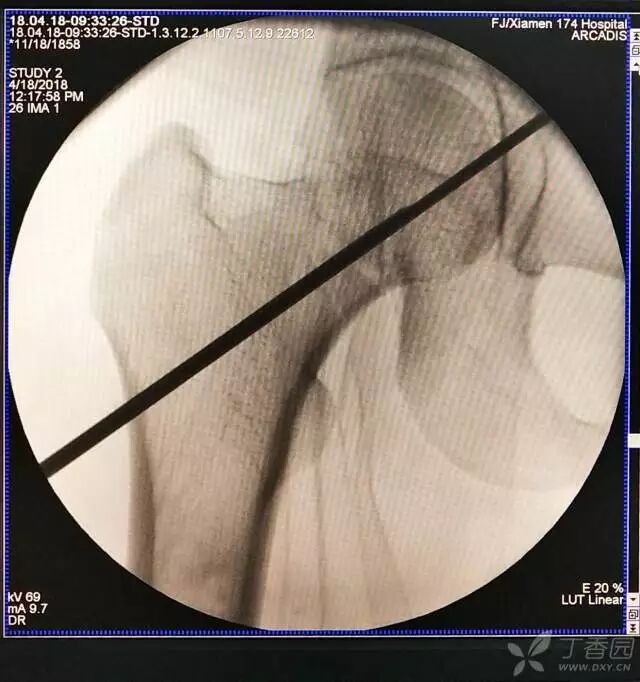

7. 摆 4 字位检查侧位导针的位置是否恰当

牵引床怎么用视频详解:如何不使用牵引床做好一台股骨颈骨折?_https://www.jmylbn.com_新闻资讯_第16张